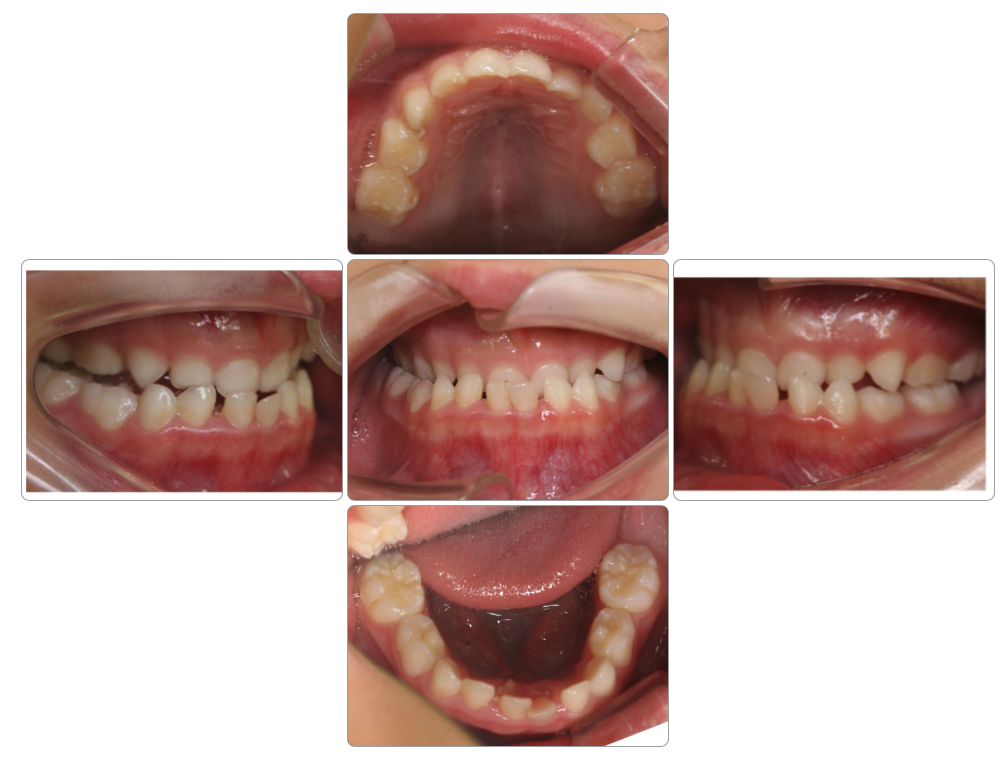

反対咬合の治療例

Before

after

| 初診時 | 6歳0ヵ月 |

| 治療期間 | 3年経過 通院中 |

| 費用 | ¥550,000・調整料¥5,500/月 |

| 使用装置 | マイオブレイス・BBI |

| リスクと副作用 | |

| 原因と考察 | 反対咬合は骨格性のものとそうでないものがあります。このお子さんは骨格性ではないのでマイオブレイスで改善しやすいと言えます。骨格性ではない反対咬合さんでは舌が口蓋をサポートしていないことで上顎部分が落ち込む(クロックワイズローテーション)ことで舌の前歯の後ろに上の前歯が入り込んで反対咬合になっている場合がほとんどですので、マイオブレイスを使用して舌が口蓋をサポートしてくると簡単に正常な状態に改善します。このお子さんの場合やや骨格も原因に入っているようですので後戻りには注意が必要ですが、基本的には姿勢・頭位を正しくすることで対応する必要があります。 |